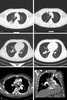

Pulmonary artery angiosarcoma